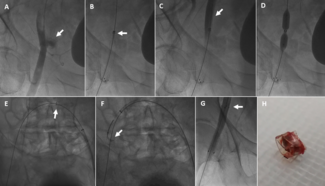

An 81-year-old woman was admitted with dyspnea and irregular heartbeat due to atrial fibrillation with a rapid ventricular response. Echocardiography showed preserved left ventricular ejection fraction, severe aortic stenosis, and moderate...